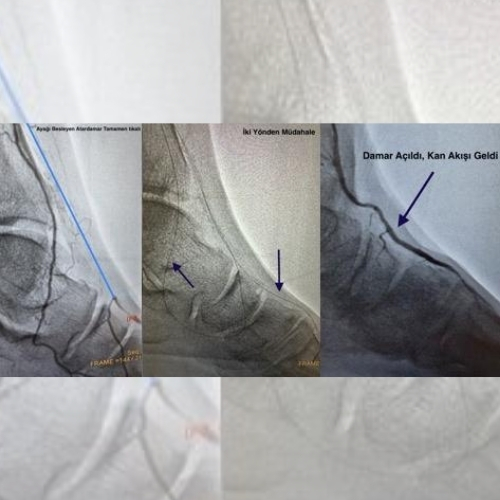

Bacak damarlarındaki tıkanıklıklar genellikle kasıktaki atardamardan girilerek yapılan işlemlerle açılmaya çalışılır. Ancak bazı hastalarda tıkanıklık çok uzun ya da çok sert olabilir. Bu durumda klasik yöntemle damarın içinden geçmek mümkün olmayabilir.

Klasik girişle açılamayan bu tıkanıklıklarda bazı özel teknikler kullanılabilir:

Ayağın atardamarından girilerek, damarın tıkalı bölümüne aşağıdan yukarı doğru ulaşılabilir.

Bacağın kendi geliştirdiği küçük yan damar yolları (kollateraller) üzerinden tıkanıklığın arka kısmına ulaşılabilir.

Bu sayede damar içeriden açılır ve kan akımı yeniden sağlanır.